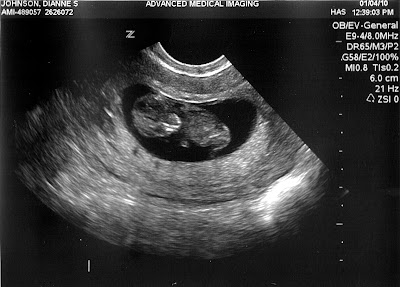

Say Hello to Baby Jesus Moses!

Don't worry, we're not going to name the baby "Jesus Moses."

Actually, "Noah" is a top contender but if you're going to go with a biblical name, why stop there.

We just had our first ultrasound and found out that he/she is just over 3cm tall and due on August 1st. This time around we are going to find out the sex, but that won't be for another ten weeks or so. We'll keep you posted.